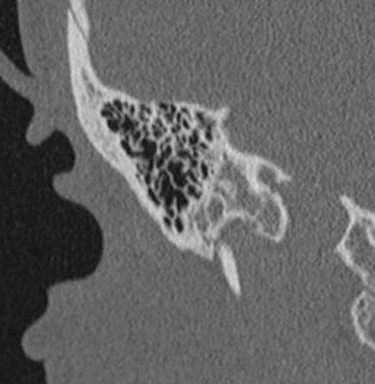

(Справа) При аксиальной КТ в костном окне у девушки 21 года с НСТУ определяется выраженная гипоплазия костной слуховой капсулы. В области мыса видны ячейки, содержащие газ (ожидаемая локализация). Структуры внутреннего уха отсутствуют. Визуализируется канал ЧН VII с расширенным верхним коленом. Обратите внимание на гипоплазию вершины пирамиды с уменьшением ее ширины.

2. КТ при аплазии лабиринта:

• КТ в костном окне:

о Двухсторонняя или односторонняя аномалия

о Отсутствие улитки, преддверия, ПКК, водопровода преддверия

о Мыс улитки: отсутствие/уплощение

о Слуховые косточки: норма или мальформация стремечка

о Крыша барабанной полости: норма, опущение или дефект (подозрителен на энцефалоцеле)

о Среднее ухо и сосцевидный отросток: норма или гипоплазия

о Канал лицевого нерва: аберрантный ход

о Вершина пирамиды: гипоплазия

о Внутренний слуховой канал: аплазия/гипоплазия

о Яремная вена/луковица: норма, зияние канала или стеноз + расширенные эмиссарные вены

о Сонный канал: норма или отсутствие

о Скат: норма или сужение

о Шейный отдел позвоночника: норма или аномалии